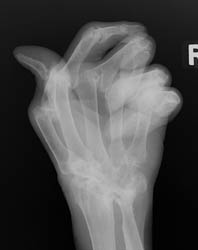

This disease is a bilaterally symmetrical and polyarticular process. Commonly

affected joints of the hand and wrist include the MCP, PIP, any of the wrist

joints, and the distal ulna and radial styloid. The distal interphalangeal

joints are rarely involved.

Advanced signs of RA include diffuse loss of joint space due to loss of cartilage. There can also be marginal or central erosions and severe joint deformities. Subluxations and dislocations may lead to ulnar deviation at the MCP joints and radial deviation at the radiocarpal articulations of the wrists. Erosive changes are also noted at the distal ulna and radial styloid. Joint deformities seen in RA include a Boutonniere deformity (flexion at the PIP joint and hyperextension at DIP joint) and a Swan-neck deformity (hyperextension at the PIP joint and flexion at the DIP joint). In severe cases, there may be radiographic findings of ankylosis at the proximal interphalangeal and metacarpophalangeal joints.